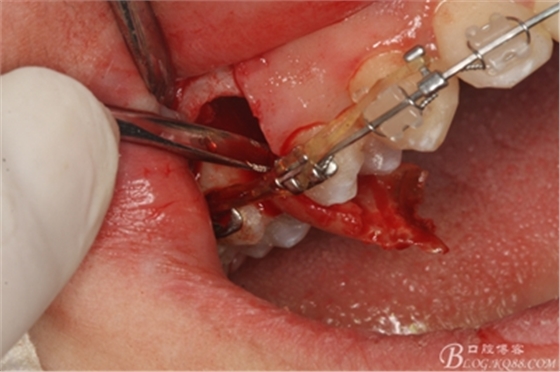

圖11.仔細考慮之后,在14頰側(cè)做垂直切口,切口長度僅達膜齦聯(lián)合處,做小切口。

圖12. 做垂直切口+齦溝內(nèi)切口,形成角形瓣,暴露出15根面。